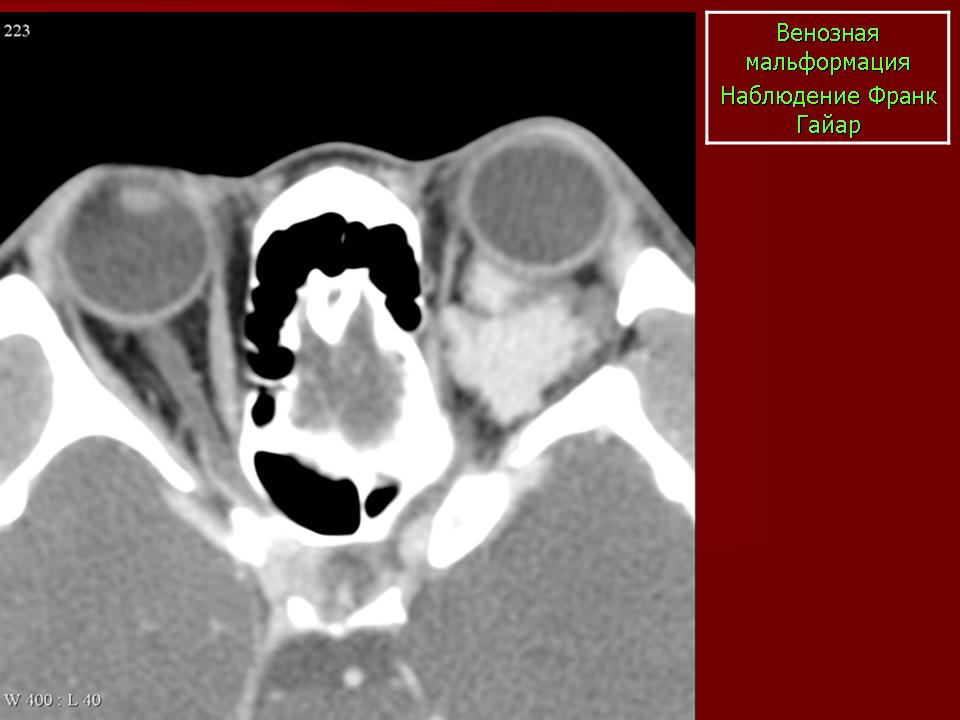

Наиболее характерный признак: объемное образование, расположенное в конусе орбиты, которое интенсивно накапливает КВ. В 80% случаев локализуется интраконально (в других случаях может иметь экстракональную, внутримышечную и внутрикостную локализацию). Ограничено псевдокапсулой, состоящей из компренированных прилежащих структур.

КТ-семиотика

Гомогенное, несколько гиперденсное образование. Гиперденсность обусловлена наличием микрокальцинатов. Грубые точечные обызвествления встречаются редко. Достигая крупных размеров, образование может вызывать доброкачественное ремоделирование глазницы.